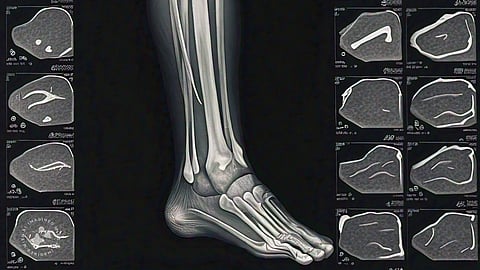

A US doctor has shared a shocking CT scan revealing the disturbing effects of undercooked pork on the human body.

Dr. Sam Ghali, an emergency physician, posted the image online, challenging his followers to identify the diagnosis. The scan showed a severe parasitic infection in the patient's legs caused by eating undercooked pork.

The patient was diagnosed with cysticercosis, a parasitic infection caused by ingesting larval cysts of Taenia Solium, also known as the pork tapeworm.